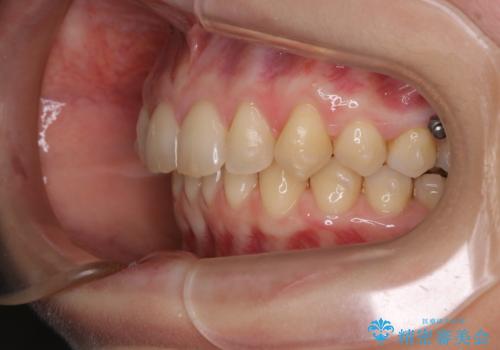

- 着色を落としてほしいとのことで来院されました。

PMTC60分コースを行いました。

着色がとても多くついていました。着色がここまでついていると、目立ちますし、マウスピースをはめたままのお水以外は飲むのは控えましょう。